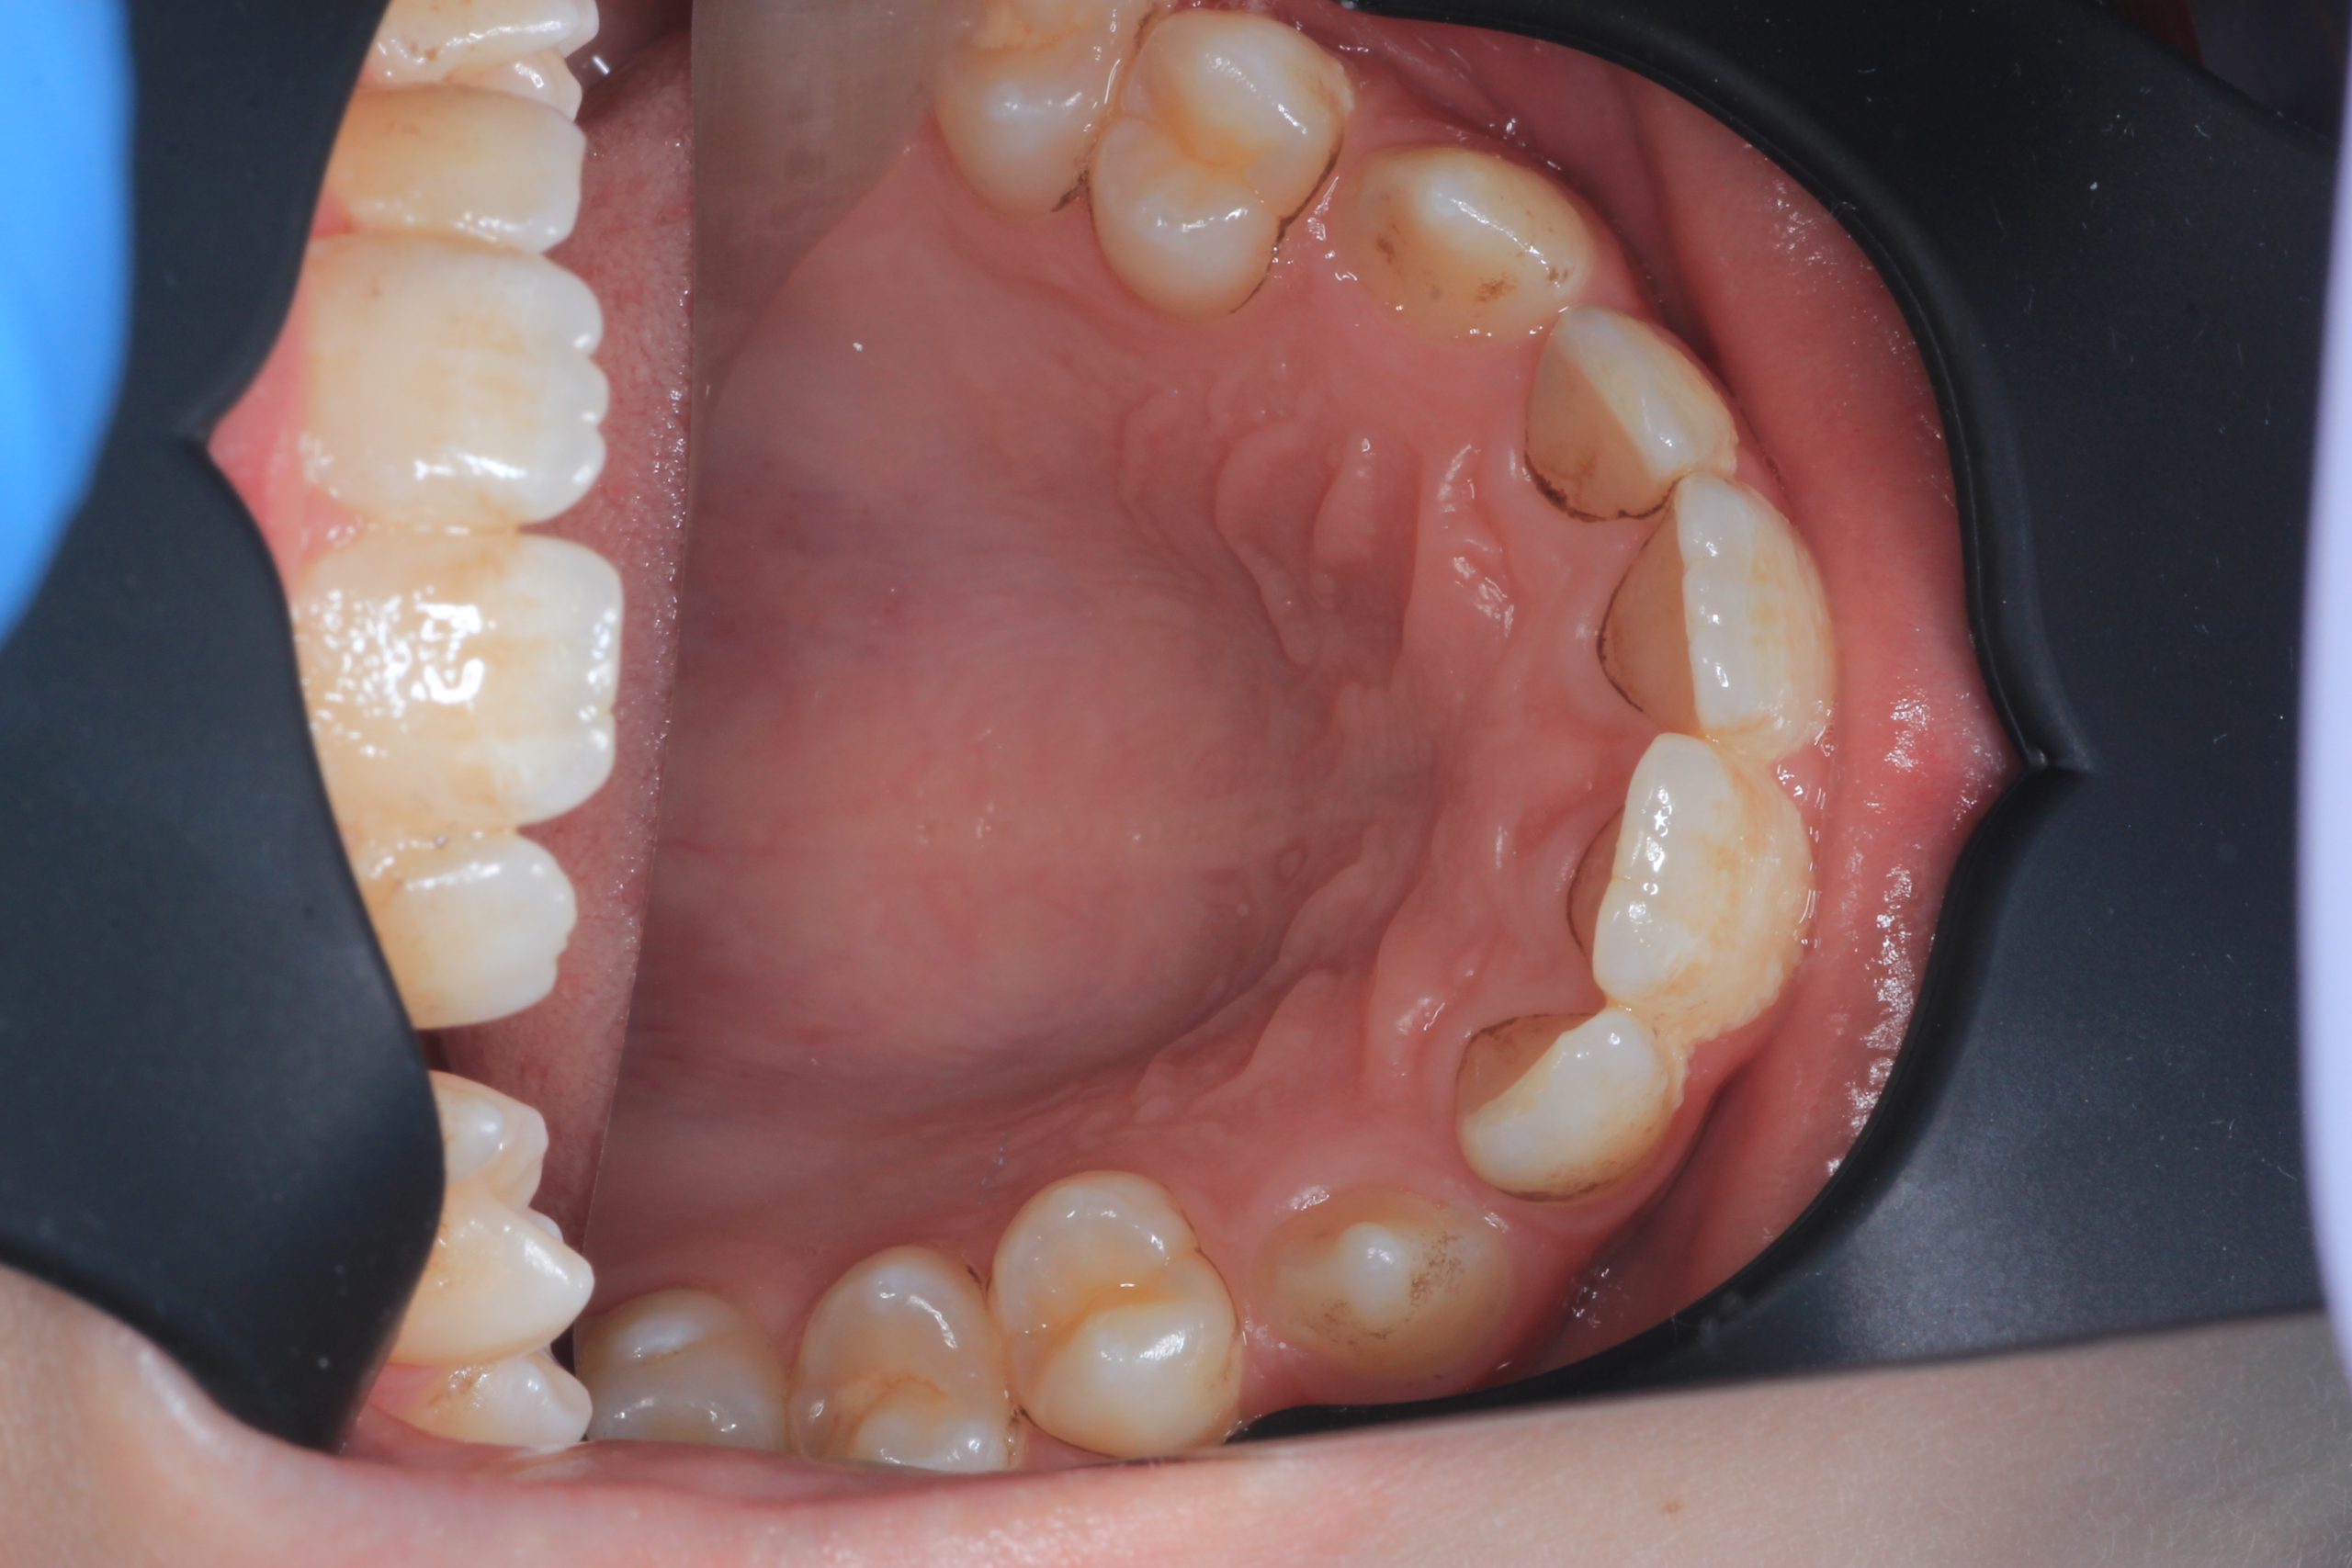

We examine the condition of teeth, gums, and bite. - Plaque Disclosure with Special Indicators

Areas that weren’t cleaned well appear purple. The darker the shade, the older the plaque. This helps both kids and parents understand where brushing needs to improve. - Brushing Training & Home Care Tools Selection

Together with your child, we practice brushing techniques, correct mistakes, and provide personalized recommendations. We advise whether to use manual or electric brushes, floss, interdental brushes, or remineralizing gels. - Plaque Removal with AIRFLOW Prophylaxis Master (EMS, Switzerland)

From age 4–5 and up, we perform full GBT cleaning using an ultra-fine erythritol powder to clean even hard-to-reach areas gently and safely. It does not damage enamel and is ideal even around braces — no need to remove brackets or wires. - Tartar Removal (If Needed)

Any tartar is removed gently and painlessly. - Final Check-Up + Fluoride Protection